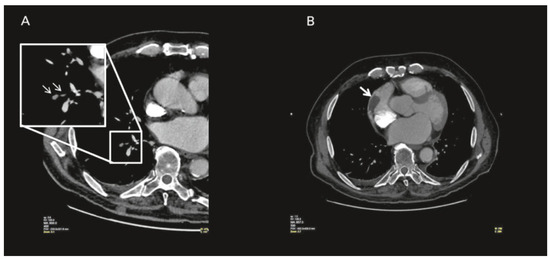

Atrial fibrillation is a cause of left atrial thrombus leading to cardioembolic stroke, which can be effectively prevented with oral anticoagulation. Right atrial appendage thrombus is a rare complication of atrial fibrillation that can also lead to cardioembolic pulmonary embolism. We present the [...] Read more.

Atrial fibrillation is a cause of left atrial thrombus leading to cardioembolic stroke, which can be effectively prevented with oral anticoagulation. Right atrial appendage thrombus is a rare complication of atrial fibrillation that can also lead to cardioembolic pulmonary embolism. We present the case of a 71-year-old male with atrial fibrillation, thrombus in the right atrial appendage and pulmonary embolism. Full article

Show Figures

Figure 1